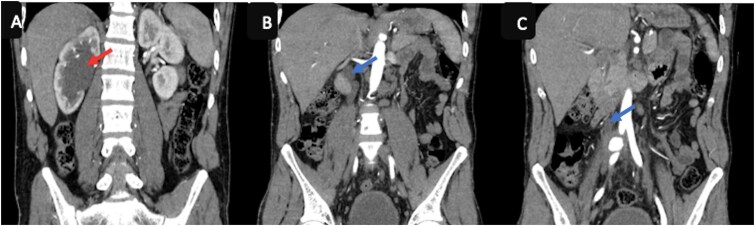

相对罕见的髂总动脉动脉瘤是血管的异常扩张,在罕见的情况下,可能会因破裂而复杂化,破裂可能被周围的结构所包含。影像学,特别是CT血管造影,在诊断中起着关键作用。我们报告一例包含破裂的髂总动脉瘤负责肾积水,髂总静脉阻塞,和邻近椎体的溶解。

Relatively rare aneurysms of the common iliac artery are abnormal dilatations of the vessel, which can be complicated by a rupture that, in rarer cases, may be contained by surrounding structures. Imaging, particularly CT angiography, plays a key role in diagnosis. We report a case of a contained rupture of the common iliac artery aneurysms responsible for hydronephrosis, obstruction of the common iliac vein, and lysis of the adjacent vertebra.